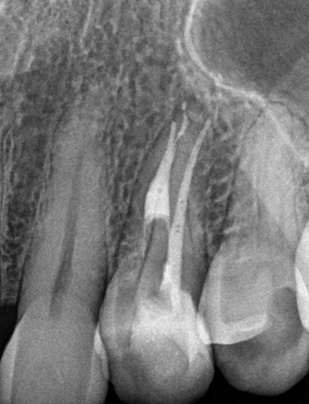

Pre-OP X-Ray

Retreatment of an upper premolar with significant loss of tooth structure and a separated instrument in the root canal.